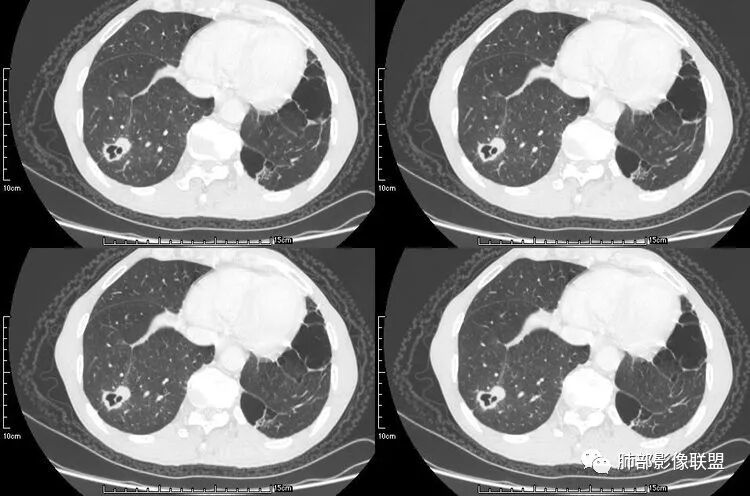

老年男性,咳嗽,咳痰带血2月,左下肺可见一团块影,深分叶,胸膜牵拉,可见坏死,坏死边界清,考虑恶性,双肺多发散在结节影,可见分叶,空洞,胸膜牵拉,考虑转移瘤;

患者老年男性,咳嗽、咳痰、痰中带血伴胸闷2月余。长期大量吸烟史。查肝肾功能、血糖、血脂、心肌酶、电解质、血沉、C反应蛋白、抗“O”、类风湿因子、抗核抗体谱无明显异常。肿瘤标志物提示NSE、CYFRA21-1稍升高。胸部CT:肺气肿背景,左肺下叶后基底段不规则肿块影,见支气管截断,内见大片状低密度区及部分血管影,增强轻度强化,远端空洞形成。双肺多发不规则实性结节影、见毛刺、胸膜牵拉及血管集束,结节内见空洞形成,部分可见血管影,多位于胸膜下。双肺见多发肺大泡。综合考虑左下肺恶性病变并双肺转移。鳞癌或淋巴瘤可能。鉴别血管炎性病变及真菌感染。

张延军:双肺多发结节,空洞影,后者洞壁厚薄不均匀,部分腔内丝丝落落,呈分叶征,边缘见毛刺影,病灶大部分位于胸膜下,与血管相连,右肺下叶前基底段结节近段支气管截断,远端见空腔。左肺下叶病灶密度不均,背段支气管壁增厚,管腔狭窄。考虑1.双肺下叶占位性病变伴肺内空洞性转移 2.多原发的占位 3.肉芽肿性血管炎代排。

本病例左肺下叶肿块,有深分叶、毛刺、胸膜牵拉凹陷、支气管截断及纵隔内淋巴结肿大等征象,都均支持病灶为恶性,如腺癌,而且叶间裂的多发结节也提示是腺癌来源可能大;双肺多发结节、肿块,大部分病灶有分叶、毛刺及胸膜凹陷的恶性征象,与原发肿瘤本身的性质有关,所以应该与左肺下叶肿块同源,而且双肺多发病灶内空洞也具有多样性;

此病例中空洞形态多样,内壁不光整,有分隔影,周围未见明显卫星灶及钙化灶,结核不太符合;患者病史慢性病史,无明显发热,缺乏中毒临床表现,急性感染基本排除;各种中性粒细胞胞浆抗体阴性,没有鼻窦炎,肾脏等病史,基本排除血管炎;霉菌性空洞常见于免疫机能低下者, 常为空洞、肺炎、伴“ 晕圈”征的结节及支气管扩张合并存在。